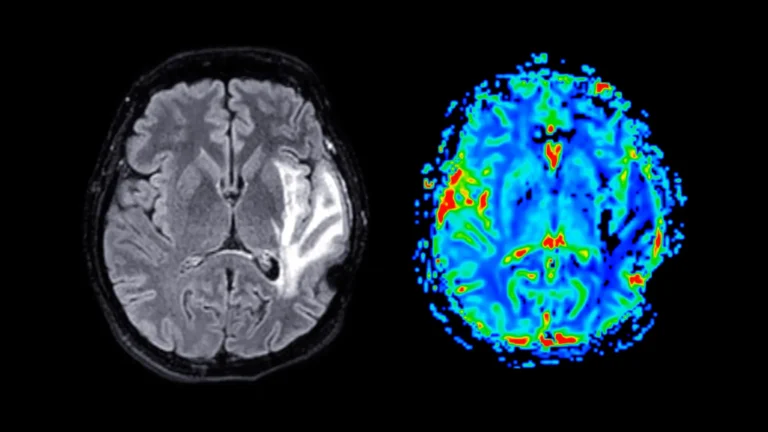

Alzheimer’s disease, a relentless neurodegenerative condition, is widely recognized for its profound impact on cognitive function, most...